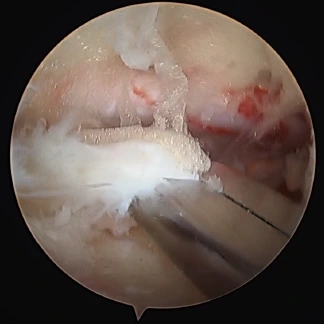

当院では、膝関節、肩関節(腱板修復術、バンカート修復術)、手指(手根管開放術)、股関節の疾患に対して「関節鏡視下手術」を行っています。関節鏡視下手術とは、まず手術をする関節の周囲に6~7mmの皮膚切開を数個作り、この小さな切開口から細いカメラ(内視鏡)や手術器具を関節内に入れて、モニターで内部を目視しながら行う手術のことです。関節鏡を用いる手術では、手術時の切開口が小さくて済むので、術後の回復が早いのが特徴です。体力的にも美容的観点からも患者さんの負担が小さいなどのメリットもあります。

UBE/BESS (Unilateral Biportal Endoscopy/Biportal Endoscopy Spine Surgery)の略称で、現在アジアを中心に脊椎手術の主流になりつつある術式です。従来の単孔式内視鏡下手術と大きく異なる点は、2孔式という点です。2か所小さく皮膚を切開し、片方から先端にカメラが付いた専用の内視鏡を挿入、もう一方から手術機器を挿入します。約5㎜と10㎜程度の小さい切開で済むため、背中の筋肉や組織の損傷を最小限に抑え、術後の痛みも軽くなります。

腰椎椎間板ヘルニアの術中画像